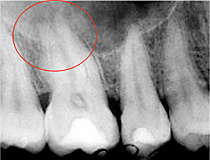

Beispiel für eine Wurzelkanalbehandlung

Oberkiefermolar mit chronischer Entzündung an der Wurzelspitze und Ausheilung nach einem Jahr